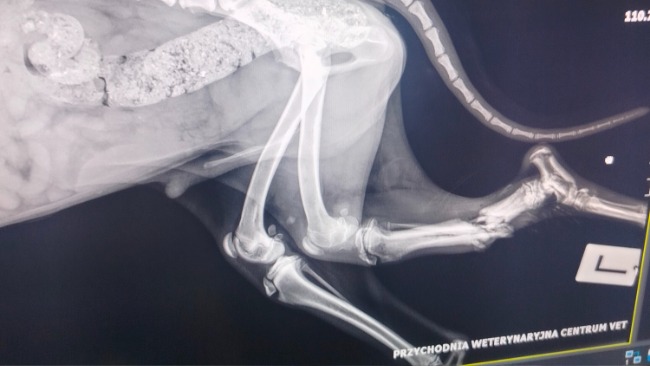

A jego łapa…

Otwarte złamanie obu kości. Rana zakażona, gnijąca. Zapach, który wbija się w głowę i nie pozwala zasnąć. Ból, którego nie da się opisać słowami.

Dziś lekarze oczyścili ranę, zabezpieczyli kość, dostał silne leki i kroplówki. Ale to dopiero początek drogi.

Może uda się uratować łapę.

Może nie.